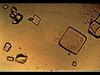

Ammonium Magnesium Phosphate Coffin Lid Urinary Crystals

Calcium Phosphate Wedge-shaped Prism Urinary Crystal

Cystine Hexagonal Urine Crystals

Uric Acid Rhomboid or Rosettes Urine crystals